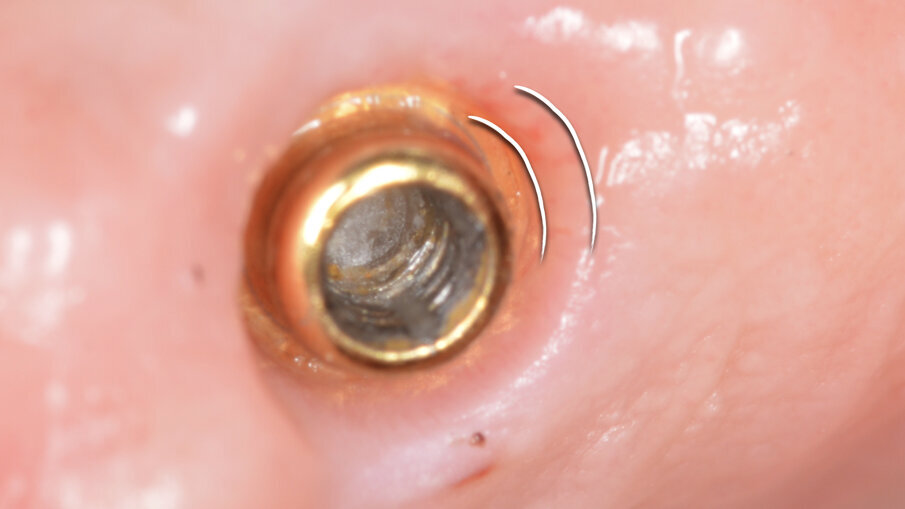

Dopo 3 mesi la situazione dell’abutment, una volta smontato l’healing abutment, è di quelle desiderabili in una protesi su impianti (Fig. 15). Terminato il lavoro con la consegna del manufatto protesico, si procede con la spiegazione, in vari appuntamenti delle manovre di igiene per il corretto mantenimento del lavoro nel tempo. Per la rimozione di placca batterica fresca si istruisce il paziente all’utilizzo di super floss per la detersione nella zona confine tra protesi e tessuti molli (Fig. 16). Super floss di oral-b è utilizzato anche per le manovre di igiene orale in studio per l’igiene dei monconi implantari.

Fig. 15_Ottimo stato di salute di OT Bridge allo smontaggio della vite di guarigione.

In particolare le polveri di glicina grazie al loro elevato potere antimicrobico e alla loro granulometria ridottissima, permettono un’accurata disinfezione a livello sopra e sub gengivale dell’intero cavo orale, soprattutto a livello del tragitto trasmucoso dell’abutment. In foto possiamo vedere un OT Equator (Rhein83, Italia) utilizzato per protesi fissa con la sistematica OT Bridge (Rhein83, Italia) (Figg. 5, 6). La rimozione totale del Biofilm batterico a livello sopra e sotto gengivale permette una “restitutio ad integrum” del tessuto gengivale, con una disinfezione profonda a livello tissutale.